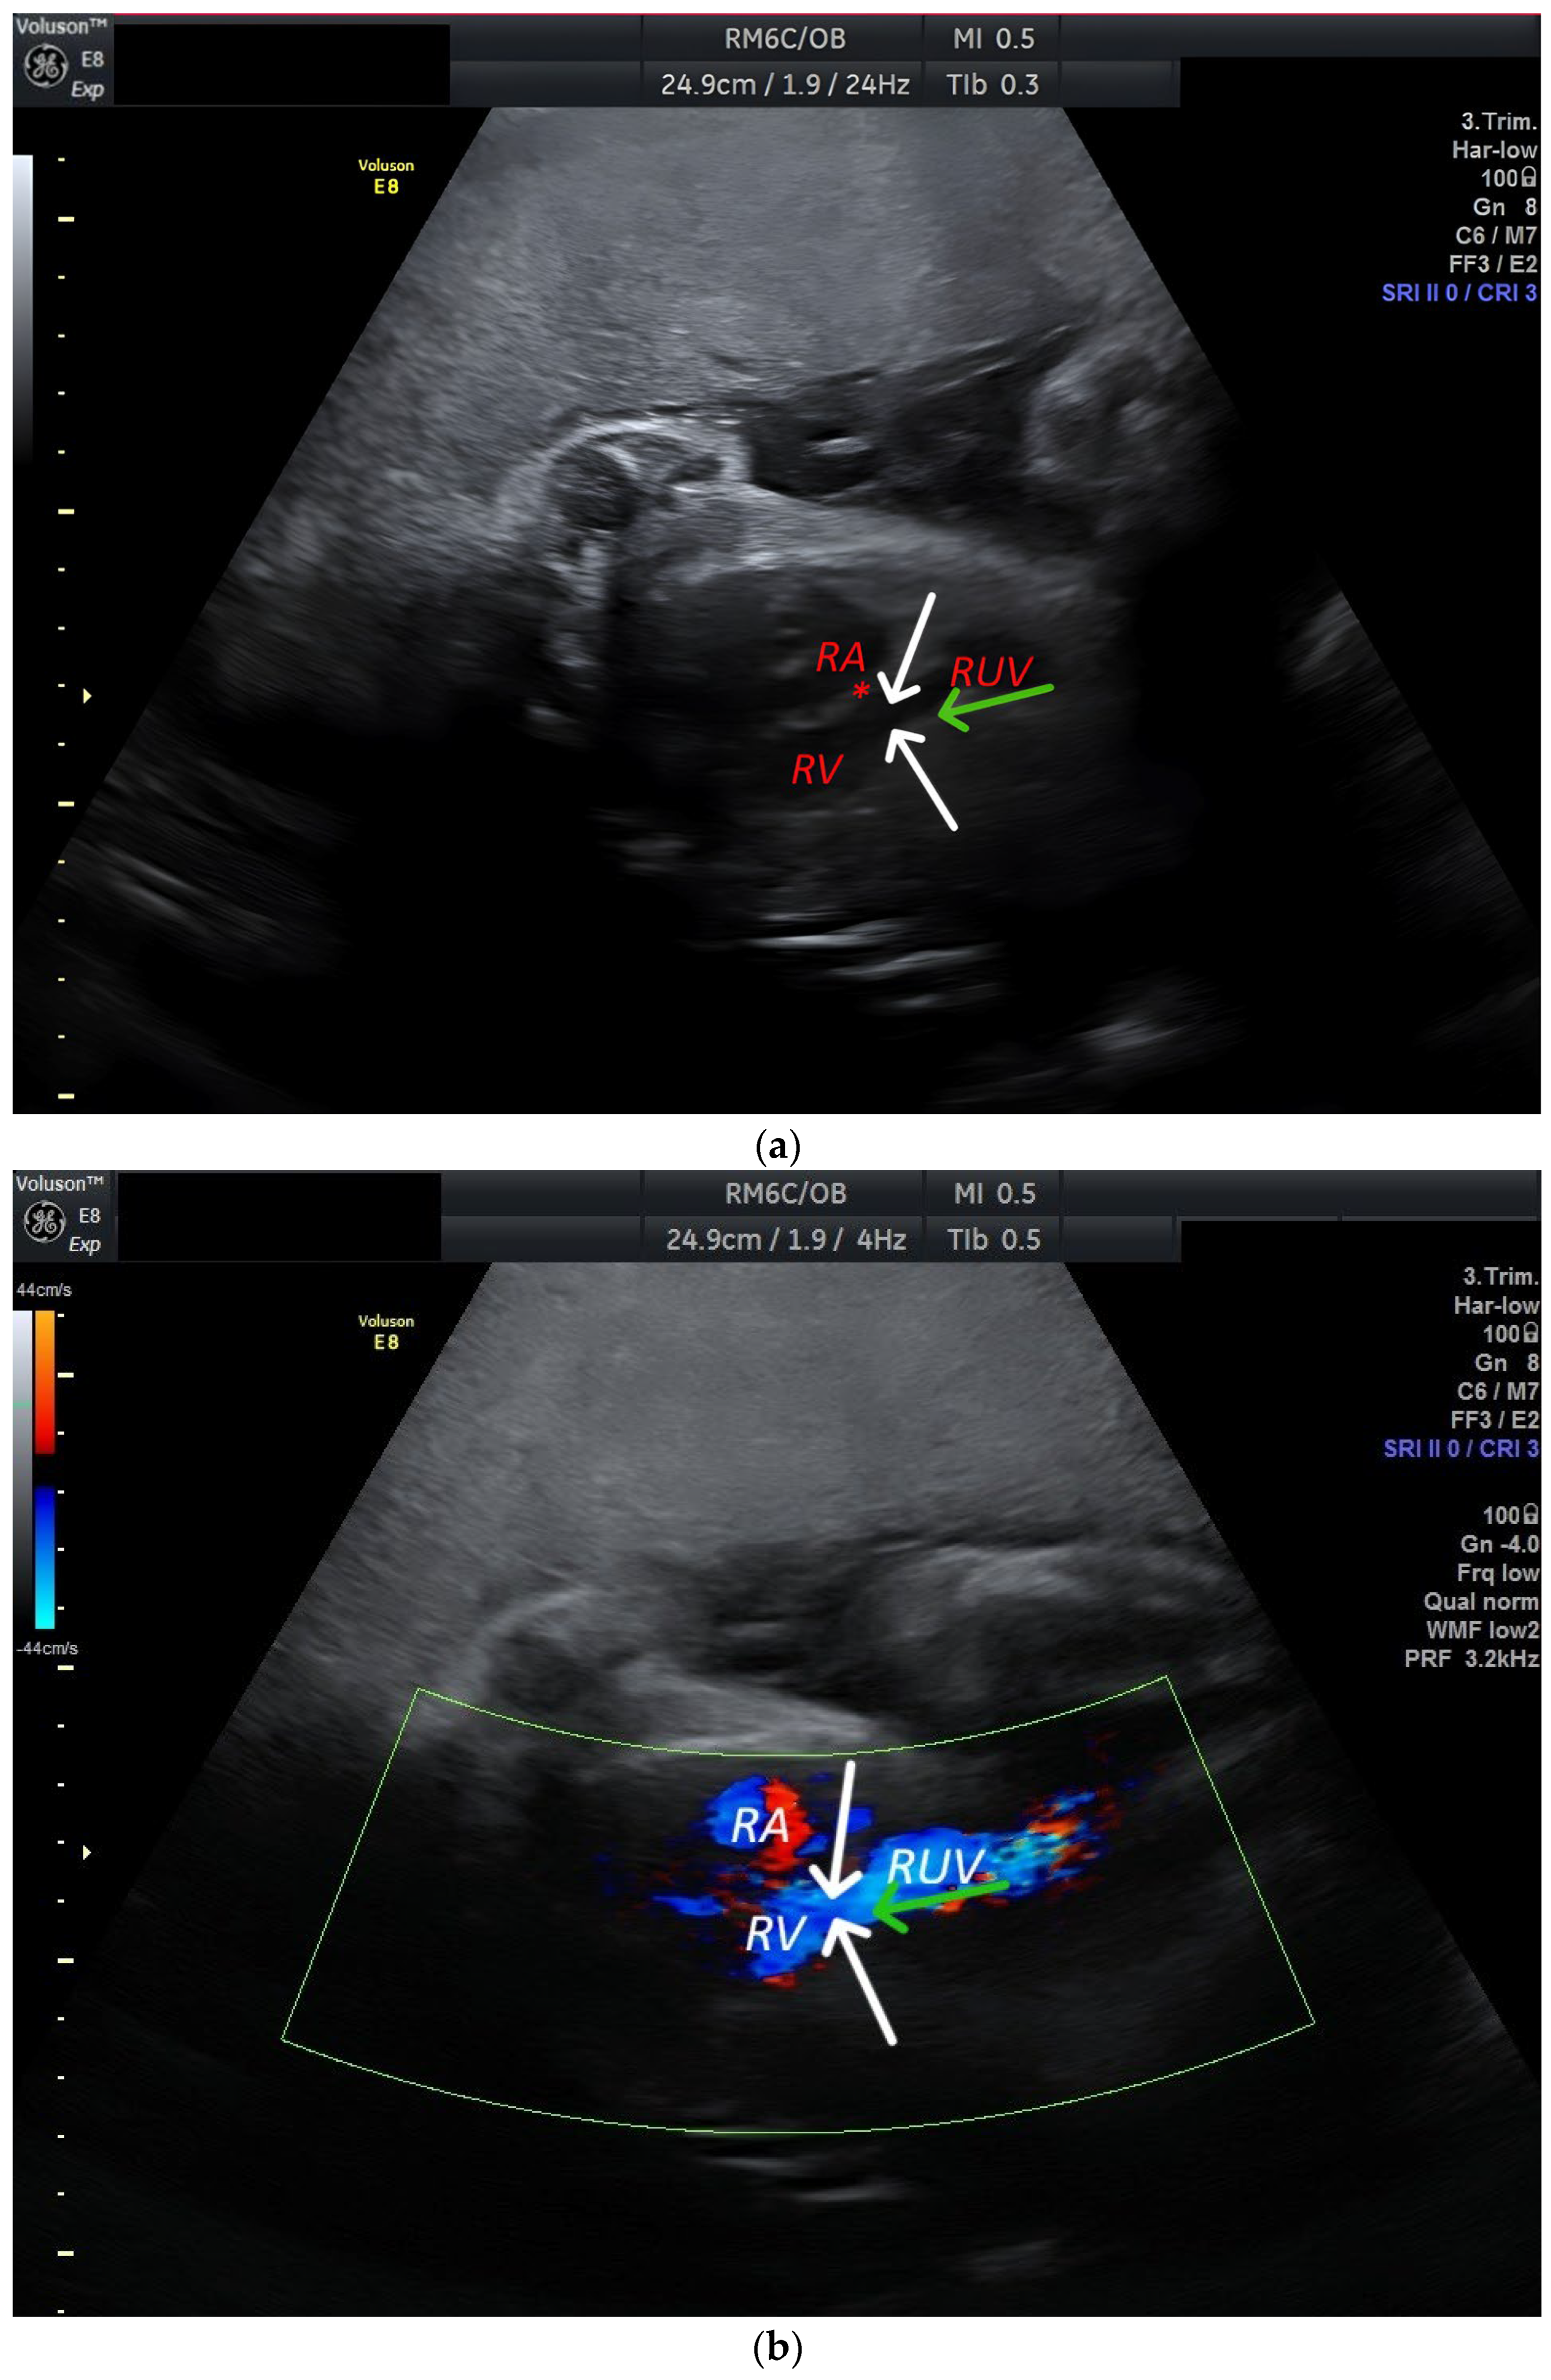

Discover what a persistent right umbilical vein (PRUV) means for fetal development. This guide explains the clinical significance of this vascular anomaly, how it is detected via prenatal ultrasound, and what expectant parents need to know about follow-up monitoring and long-term outcomes to ensure a healthy pregnancy journey.

Read full article: Persistent Right Umbilical Vein